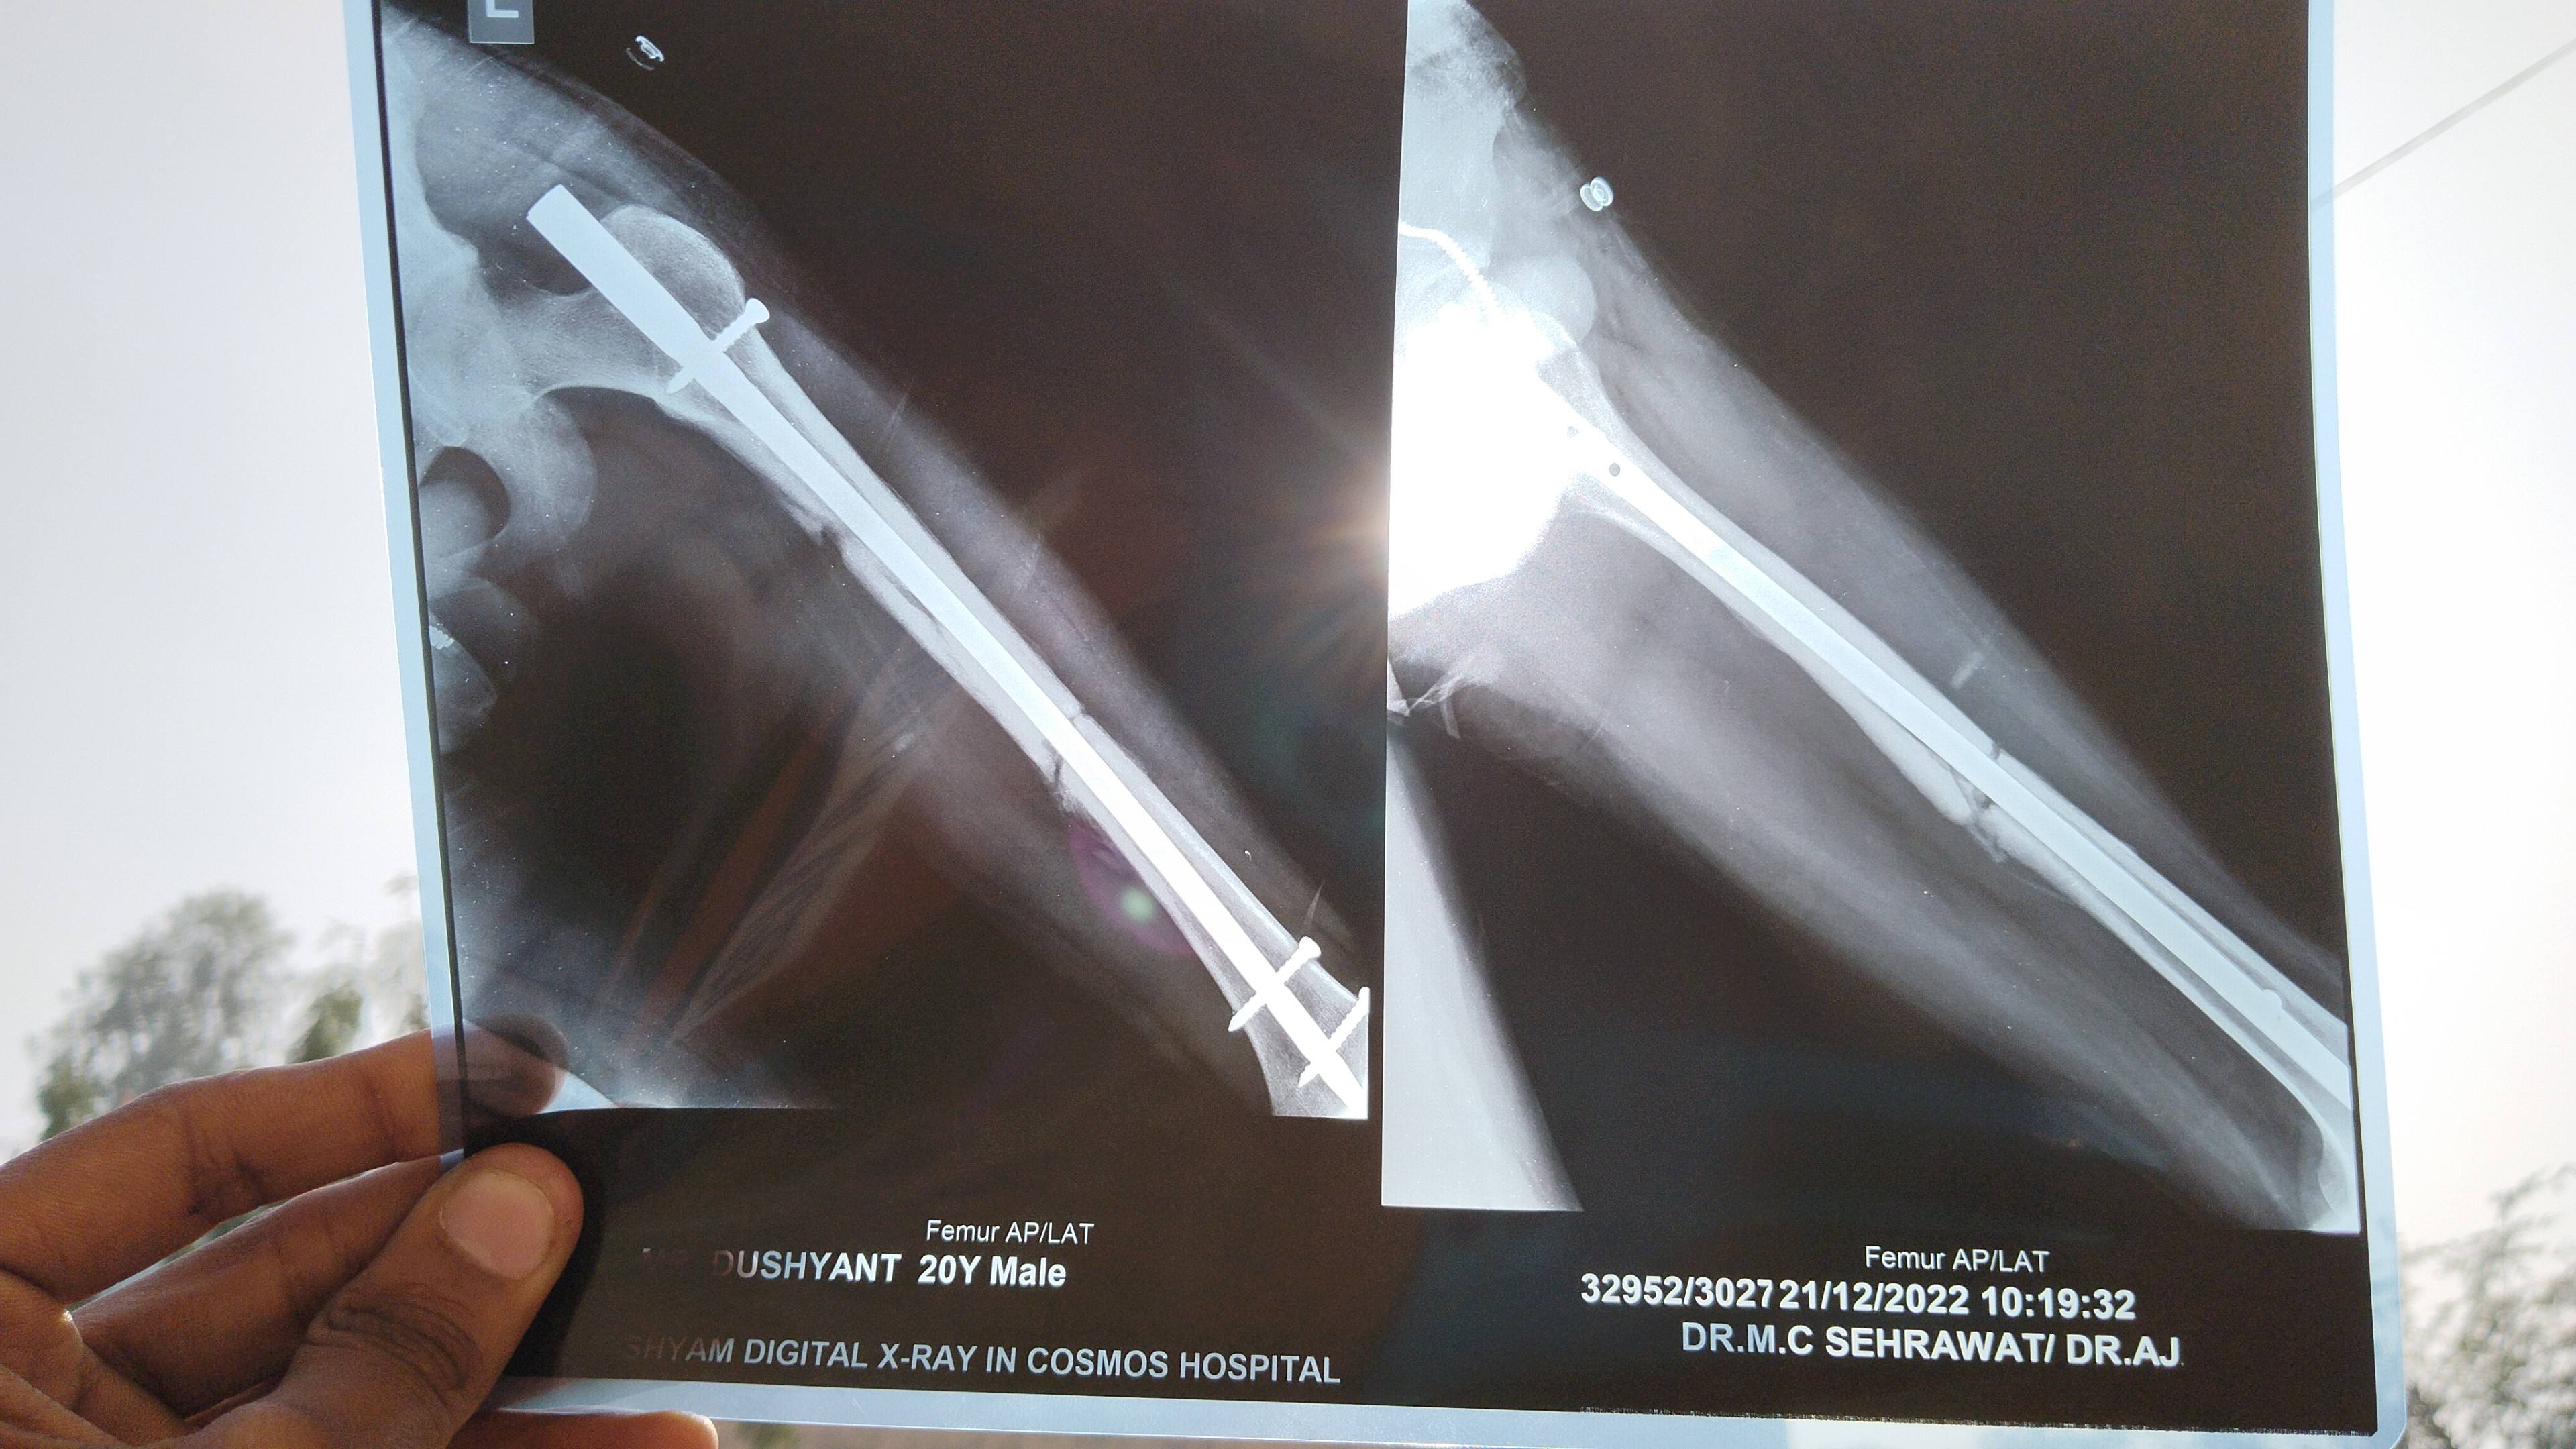

Dushyant from palwal

Sir mere femoral shaft fraxture ka aaj x ray hua h aur mujhe aaj 4 month 11 days ho gye hn

kya isme bone grafting kra leni chiye ya fir isme wait krna chiye vo bhi kitne month ka